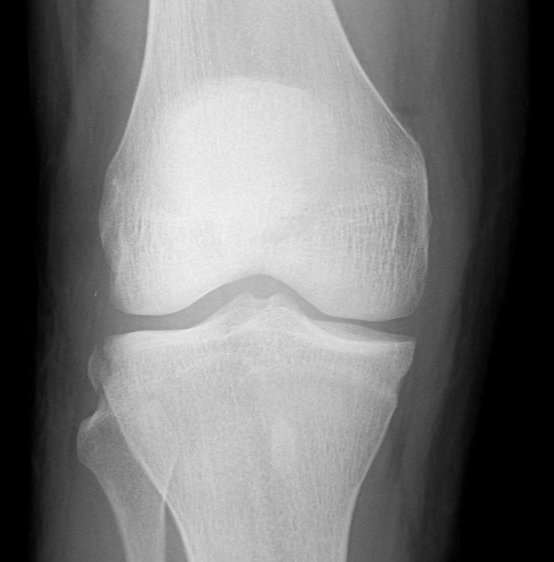

Segond Fracture

This is a very subtle "avulsion fracture of the tibia below the articular margin" caused by traction on the capsular or coronary ligaments. It is not possible to cause this fracture without first rupturing at least one of the major ligaments in the knee.

Examples in order of increasing subtlety: -